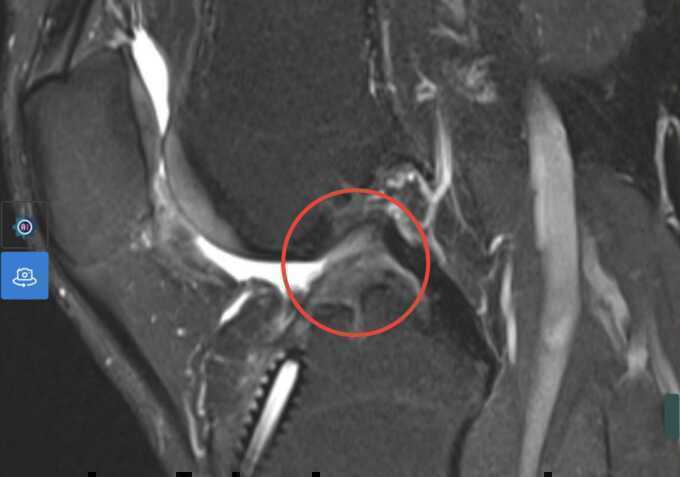

Bác sĩ chụp MRI và CT dựng hình khớp gối để khảo sát đường hầm cũ và các cấu trúc quanh gối bệnh nhân, lên phương án lựa chọn mảnh gân, thiết bị cố định, định hướng đường hầm chính xác nhất có thể. Đầu tiên, bác sĩ nội soi đánh giá trực tiếp các tổn thương trong khớp, loại bỏ các thiết bị cố định dây chằng từ ca phẫu thuật trước và làm sạch, tạo đường hầm theo CT hướng dẫn. Sau đó, bác sĩ lấy một đoạn gân tứ đầu nông nằm ở phía trước đùi, trên xương bánh chè để làm mảnh ghép dây chằng theo kích thước đã đo.